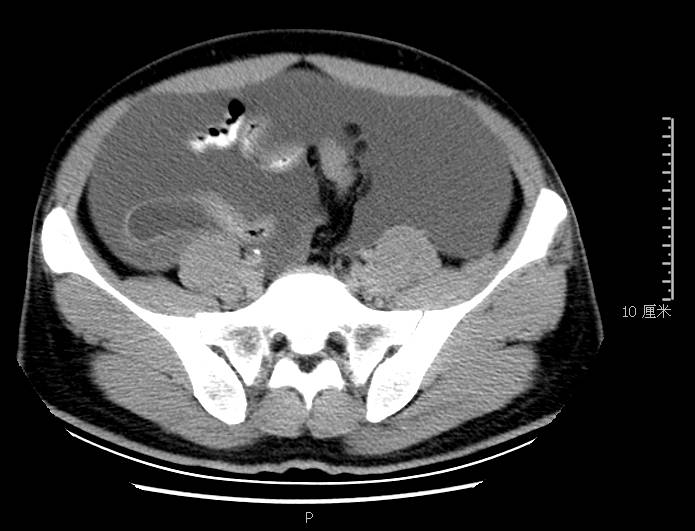

全腹CT:(1)结合病史考虑腹膜炎(见图2A),大量腹水;(2)右骼窝区管状样结构,考虑阑尾扩张(见图2B);(3)肝脏多发小囊肿(见图2C);(4)肝内胆管轻度扩张,建议隔期复查。

图2b扩张成管状阑尾

PET-CT检查:(1)腹盆腔大量积液,腹膜略厚,其间散在小淋巴结,代谢轻度增高,倾向腹膜炎可能性大,建议治疗后复查并密切复查肿瘤标志物;(2)双侧颈部领下、双侧腋窝淋巴略增大,代谢轻度增高,考虑炎性病变;(3)右肺下叶胸膜下钙化灶;(4)肝内多发囊肿,胆囊壁略毛糙;(5)右侧骼窝区细条形软策划影,代谢稍增高,考虑阑尾扩张。电子胃镜:(1)胃息肉(1枚己摘除);(2)反流性食管炎(*级A**);(3)慢性胃炎。电子肠镜未见结核、肿瘤性病变,未见阑尾开口扩张及周围策划红肿糜烂性病变,见图3。

本例确诊后对B超及CT再次回忆发现:腹腔、盆腔可见不均质中强回声包块,部分呈囊实状,腹膜增厚,大网膜成饼状(如图2A)和肝周可见不均质中强回声弧形压迹、脾周可见不均质中强回声包饶,肝脏成扇贝样改变(如图2C),但在诊断报告中未提及。有学者发现mantle和scalloping(如图2A,2C)在PMP中具有代表性,且mantle较scalloping更为常见,若mantel征同时伴有大小不一的囊性改变,则更具诊断价值。

与此同时,还应与肝硬化腹水、妇科肿瘤、肠梗阻等疾病相鉴别。此患者为男性,全腹CT及PET-CT均提示阑尾扩张,很大可能来源于阑尾黏液性肿瘤。阑尾黏性肿瘤早期可无任何症状,随着瘤体堵塞阑尾,累及浆膜下层,播散至腹盆腔,可形成大量的黏液性腹水,又称“胶腹”,则可出现腹痛、腹胀、腹围增加等症状。

通过本病例分析认为此类患者,腹穿时若发现腹水不易抽出或抽出物为黏稠胶冻样,腹部B超提示液性暗区内有漂浮的团状回声有分隔,撞击腹部后可出现“礼花”样改变,肝脾包膜完整不光滑,有弧形压迹,全腹部CT示弥散占位,可见mantle和scallping征、大网膜成饼状且阑尾扩张应高度怀疑本病。